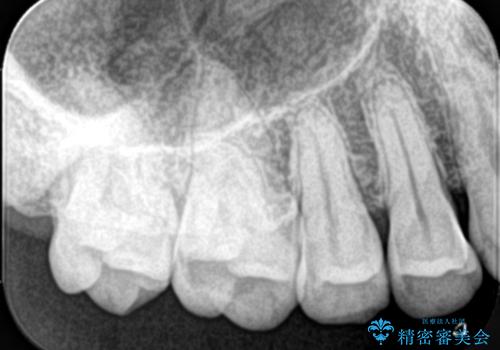

右上5番にう蝕があり、審美性・適合性・材料安定性の高いセラミックインレーでのやり替えとなりました。

右上5番の近遠心にう蝕が認められたため、CR裏層の後MOD窩洞のセラミックインレーとしました。